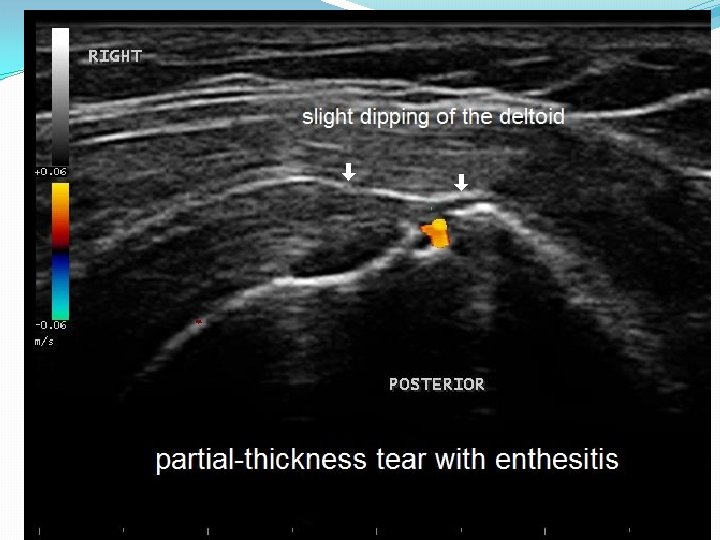

Subacromial Impingement Syndrome Marwan Alqunaee, RCSI, Rose Galvin, BSc (Physio), Ph. D, Tom Fahey, MD, FRCGPDiagnostic Accuracy of Clinical Tests for Subacromial Impingement Syndrome: A Systematic Review and Meta-Analysis Archives of Physical Medicine and Rehabilitation, Volume 93, Issue 2, February 2012, Pages 229– 236 �Any rotator cuff pathology in the subacromial space �Includes Supraspinatus, Infraspinatus, Teres Minor and Subscapularis �Stages Include �Stage 1 -Bursitis �Stage 2 -Partial Tear �Stage 3 - Full thickness Tear

Subacromial Impingement Syndrome=SIS �History- pain with overhead activity, nocturnal pain �Exam-Hawkins Kennedy passive forward flexion/int rotation only useful test in a hemiplegic patient Sensitivity 74% �Imaging- Ultrasound can identify all 3 stages of SIS bursitis, partial tear and full thickness tear

Diagnostic accuracy of Ultrasound for RCT Smith et al, Clin Radiol 66 (2011) 1036 -1048 �Given limitation of history (communication deficit) and exam (given UE weakness), imaging assume greater importance �Partial thickness RCT Sen 84%, Sp 89% �Full thickness RCT Sen 96%, Sp 93%